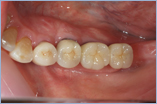

現在はインプラント治療は一般的に行われています。

治療中はムシ歯の治療など使用している局所的な麻酔で行えます。ほとんどの場合可能ですが専門医がくわしく診断し最善の方法をおすすめします。

※インプラントをより長くお使いいただくために定期的にクリーニングに来ていただき状態をチェックさせていただきます。

インプラント

¥280,000(被せ物は除きます)

※消費税は別にかかります。